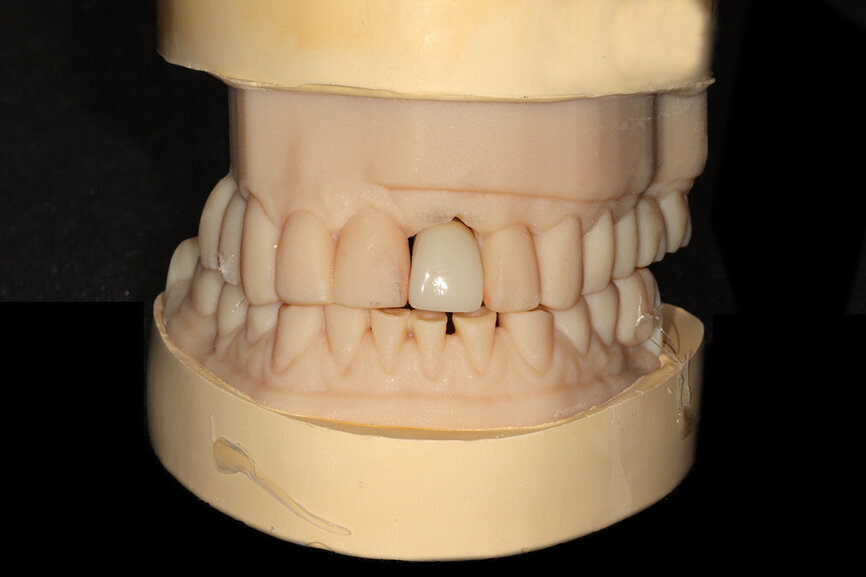

Fig. 16a: The accuracy of the implant and template design allows for true restoratively driven planning combined with CAD/CAM applications for the design

and fabrication of a patient-specific abutment and transitional restoration.

Fig. 16b: The accuracy of the implant and template design allows for true restoratively driven planning combined with CAD/CAM applications for the design

Fig. 26a: The prefabricated CAD/CAM abutment and transitional crown

Fig. 26b: A post-op periapical radiograph confirmed successful sub-crestal placement of

this platform-switched design.

Fig. 26c: The abutment in place.

Fig. 26d: The soft-tissue contours were excellent; no sutures were required for the transitional restoration.